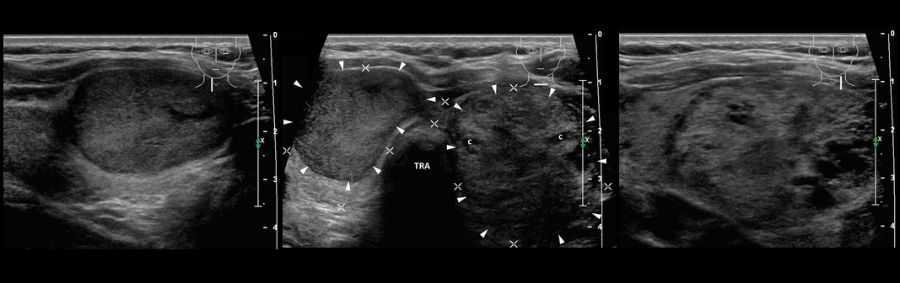

- Изоэхогенное образование щитовидной железы с гипоэхогенным ободком. Это часть нормальной ткани органа, который окружает определяемый контур, указывающий на то, что там имеется узел. Ободок формируется как результат увеличения объема кровотока, а также рост сети капилляров по периметру фрагмента нормальной ткани.

- Образование с кровотоком является наиболее часто встречающейся формой патологии. Такая особенность говорит о склонности узла к изменению внутренней структуры и делению. Участки усиленного кровотока могут локализоваться на разных участках образования.

Изоэхогенное новообразование, имеющее периферический гипоэхогенный ободок

- нарушение сердечного ритма,

- Оценивается кровоснабжение железы и особенности вакуляризации новообразований, если они обнаружены.

- Описывается степень васкуляризации (кровоснабжения) очагов. Злокачественные опухоли, как правило, имеют обильную сеть кровеносных сосудов, и по этим признакам их можно дифференцировать от доброкачественных новообразований. Также применяется эластография, с помощью которой измеряются эластические свойства опухоли. При злокачественном процессе новообразование на порядок жестче, ее эластичность ниже в 18-28 раз.

Одна из важных особенностей опухоли — является васкуляризация или кровоснабжение узла. Большинство злокачественных узелков резко васкуляризованы, хотя есть и аваскулярные (бескровные) опухоли. Кроме того, усиленная васкуляризация обнаруживается в активно функционирующих (токсических) узлах, которые часто оказываются коллоидными, а не злокачественными. Таким образом, экологических данных недостаточно для подтверждения окончательного диагноза, но выявление потенциально опасных узлов — прерогатива врача-сонографиста.